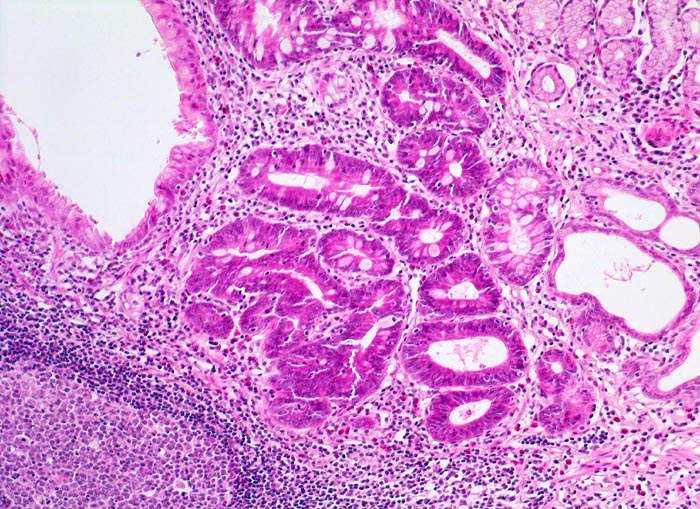

Chronische Helicobactergastritis: intestinale Metaplasie

Magenantrumschleimhaut mit dichtem Entzündungsinfiltrat mit Lymphfollikelbildung in der Lamina propria. Das Epithel eines Teils der Drüsen weist deutlich dichteres Zytoplasma mit Einschluss einzelner Becherzellen auf entsprechend einer intestinalen Metaplasie. Einzelne dilatierte Drüsen (= Magendrüsenkörperzysten).

Lymphfollikel sind typisch für die Typ B Gastritis. Die intestinale Metaplasie hingegen ist unspezifisch. Sie kann auch nach Abheilung von Ulzera und Erosionen oder bei einer Autoimmungastritis auftreten. Eine Unterscheidung von kompletter und inkompletter Metaplasie ist nur mittels Spezialfärbungen eindeutig möglich und wird wegen fehlender klinischer Relevanz nicht vorgenommen.

Magendrüsenkörperzysten können dem Endoskopiker als kleine Polypen erscheinen